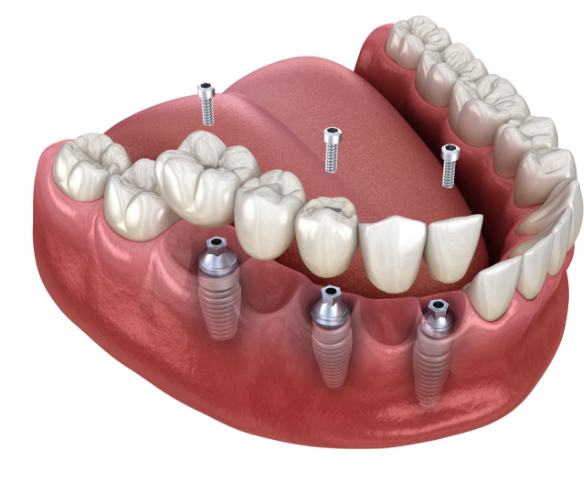

전악 임플란트

치아가 전혀 없거나 소수일 경우, 임플란트를 이용하여 전체 치아를 복원해주는 시술입니다.

자연치아는 위/아래 14개씩 모두 28개가 존재합니다.

자연치아가 상실될 경우, 본래의 치아처럼 회복하기 위해 다수의 임플란트를 식립해야 합니다.

전악 임플란트는 큰 범위의 시술인 만큼 많은 수술 경험으로 기술과 노하우가 필요합니다.